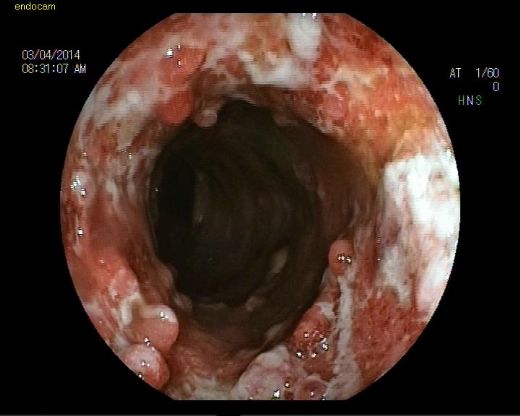

Ülseratif kolitli hastaların tanısı kolonoskopi ve bu işlem sırasında alınan biyopsiler ile konulur. Hastaların gastroenteroloji uzmanı takibinde olmaları önemlidir.